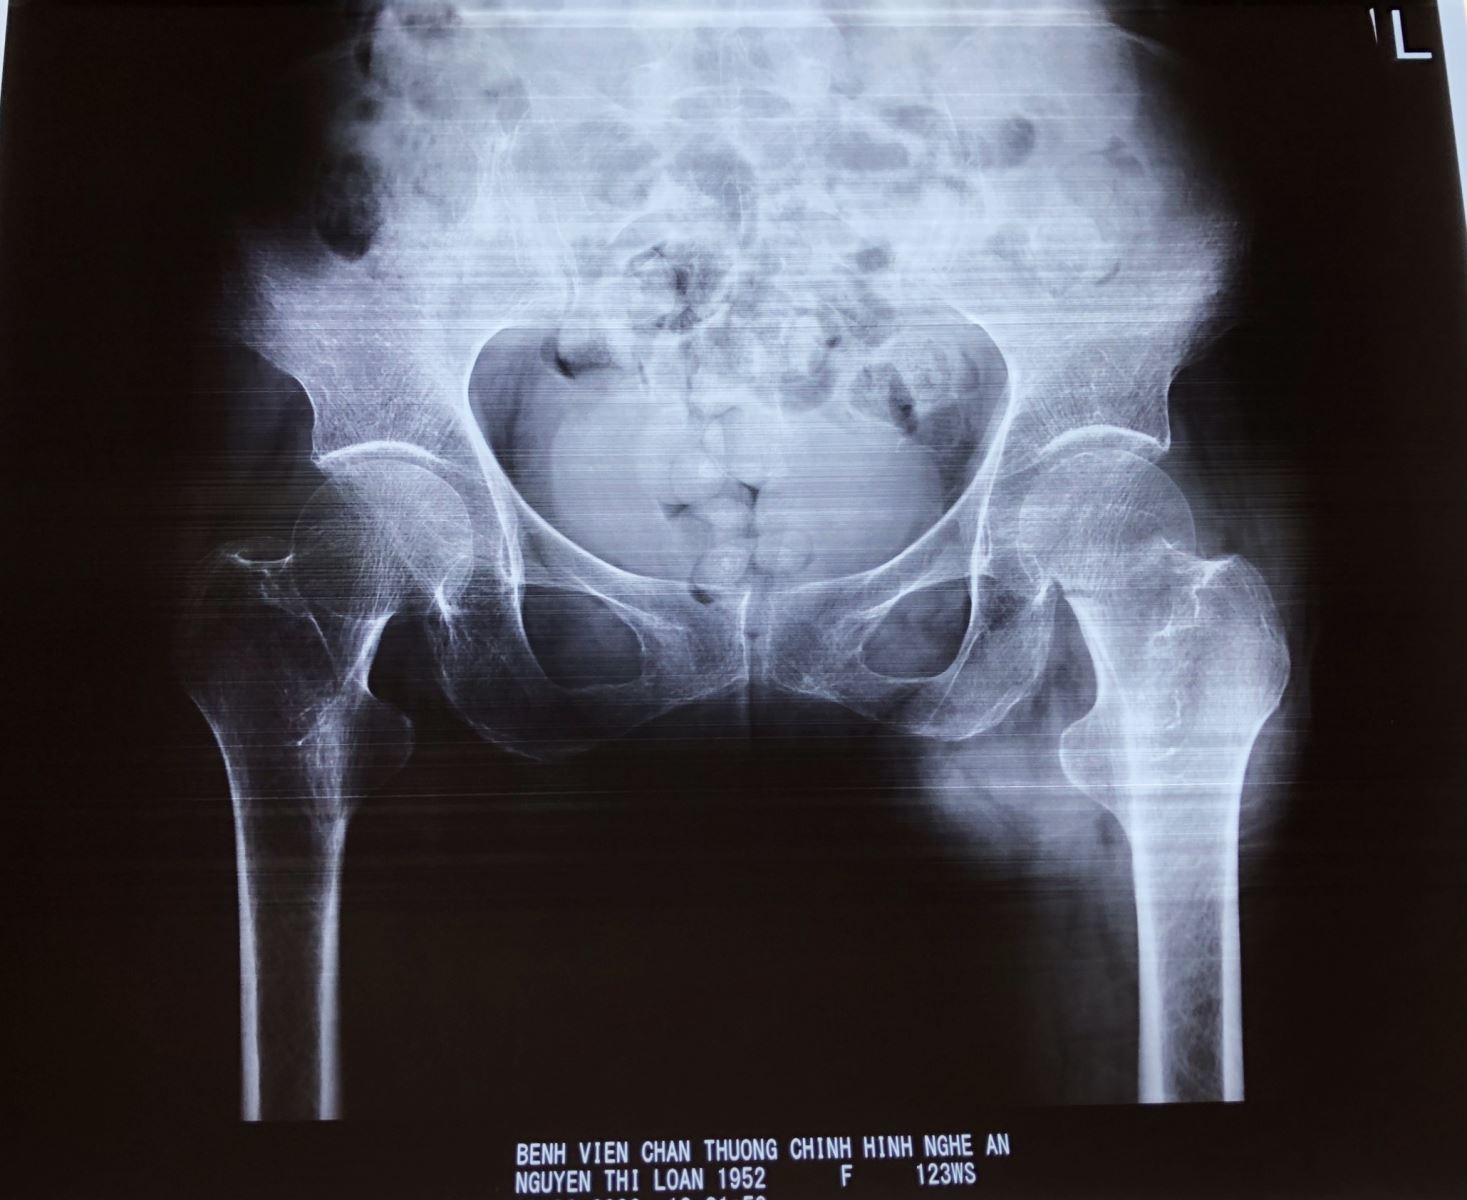

Bệnh nhân Nguyễn Thị Loan, 68 tuổi, ở TP.Vinh – Nghệ An có tiền sử parkinson, đã điều trị 6 năm nay. Đợt này bệnh nhân trượt chân ngã gây đau biến dạng, hạn chế vận động đùi háng trái. Vào Bệnh viện Chấn thương Chỉnh hình Nghệ An, bệnh nhân được chẩn đoán gãy cổ xương đùi trái.

Hình ảnh phim chụp Xquang của bệnh nhân trước và sau phẫu thuật thay khớp háng